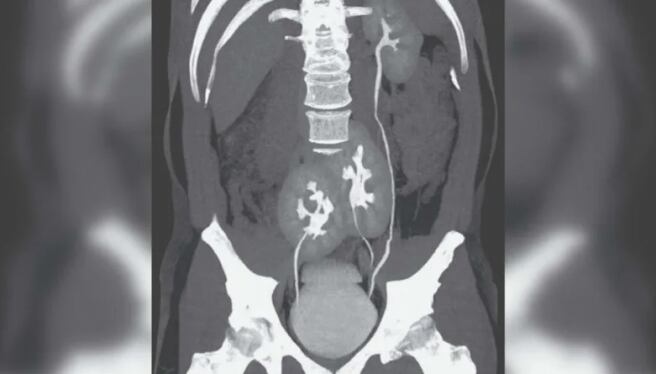

Una gran sorpresa fue la que se llevó un hombre de Brasil tras acudir al hospital por un fuerte dolor de espalda. Y es que una tomografía terminó revelando que lo que sucedía era que tenía tres riñones en su abdomen. El impresionante hallazgo fue difundido por The New England Journal of Medicine.

Los doctores del hospital do Rim, ubicado en San Pablo, explicaron que en un inicio creyeron que la molestia del sujeto de 38 años se debía a una hernia de disco, pero al hacer una revisión pudieron ver que tenía tres riñones: uno izquierdo, de apariencia normal, y dos fusionados.

Renato Foresto, uno de los médicos que realizó el descubrimiento y el posterior informe para la revista científica, expresó lo que sintió al ver la tomografía: “Nunca habíamos visto algo así. Fue una sorpresa, seguida de la preocupación de que hubiera algo mal con la salud del paciente”.